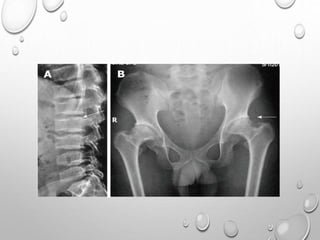

VERTEBRAE

LUMBOTHORACIC KYPHOSIS

LUMBER HYPER LORDOSIS

LENGTH GENERALLY NORMAL

PLATYSPONDYLY , DISC HEIGHT EQ TO VERTEBRAL BODY

POSTERIOR SCALLOPING

PEDICLES ARE SORT , THICK , INTERPEDICULAR DISTANCE DECREASED

ANGULAR KYPHOSIS AT THORACOLUMBER JUNCTION RESULTING FROM

ANTERIOR BEAKING OR BULLET NOSE VERTEBRAE

SPINAL CANAL STENOSIS ---- PATHOLOGIC HALLMARK

PELVIS

SMALL

ILIA ARE SHORT CAUDALLY

HORIZONTALLY PLACED ACETABULLA , THICKENED Y CARTILAGE

• 1. DYSPLASTIC OR SQUARE

ILIAC BONES

2. NARROW SACRO-SCIATIC

NOTCHES

3. FLAT BILATERAL

ACETABULAR ROOFS

4. SHORT BOTH FEMORAL

NECKS

5. CHAMPAGNE GLASS-

SHAPED PELVIC CAVITY